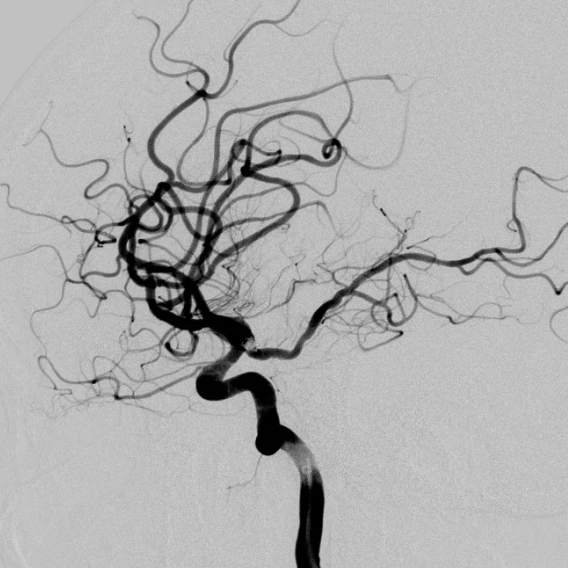

动脉瘤经过多年修炼,形态奇葩,大动脉瘤上长着小动脉瘤,小动脉瘤上长着微小动脉瘤,还累及粗大的胚胎型大脑后动脉,经过一期单纯栓塞,消除了出血风险,老人家顺利出院康复。

近日,老人家恢复了差不多了,为了防治日后宽颈的脑动脉瘤复发,还需要稍微进行一下修修补补,减少血流对薄弱的脑动脉瘤的冲击,那就需要再简单加固一下。

装备虽好,那还的找靠谱的医生给安装进去吧。今日,我们顺利为老人家在病变部位的血管植入了血流导向装置,手术顺利。然而,不是每一个破裂的脑动脉瘤患者像老人家一样这么幸运,能够有机会赶到医院,得到及时的治疗……